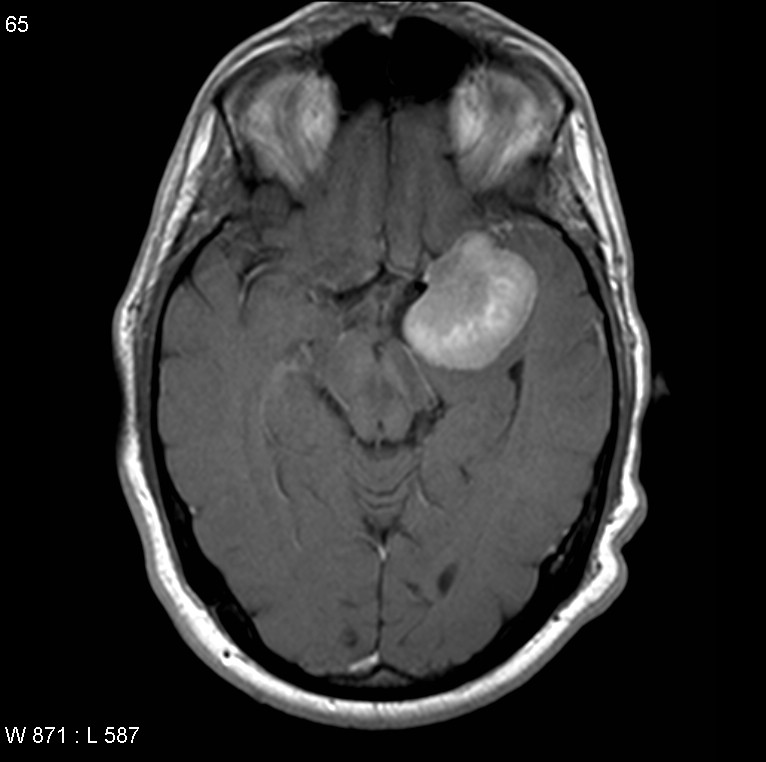

脑膜瘤是脑内比较常见的良性肿瘤,其生长缓慢,是脑外肿瘤,起源于蛛网膜,可发生于全部具有蛛网膜细胞的位置。蝶骨嵴位于前颅窝和中颅窝交界处,由蝶骨大翼和蝶骨小翼构成,...

蝶骨嵴脑膜瘤严重吗?下文报告了一例患者,其中蝶窦蝶骨嵴脑膜瘤是通过分期手术切除的,包括颅内部分的开颅手术和蝶窦颅外部分经蝶和经蝶入路的内窥镜鼻内切除术。接下来,打开左侧鼻...